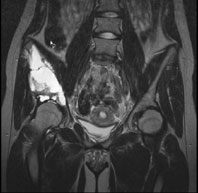

Ein 13-jähriges Mädchen kommt humpelnd zu Ihnen in die Praxis mit Schmerzen in der rechten Hüfte, die seit einigen Monaten bestehen und besonders bei Belastungen auftreten. Eine sichtbare Schwellung besteht nicht, kein Sturzgeschehen in der Anamnese.

Die Röntgenuntersuchung von Becken/Hüfte zeigt eine septierte geographische Osteolyse in der Ala und im Korpus des Os Iliums rechts. Das Röntgenbild und die Aufnahmen der nachfolgenden MRI-Untersuchung sehen Sie hier:

T2 FS, coronar, 5 mm